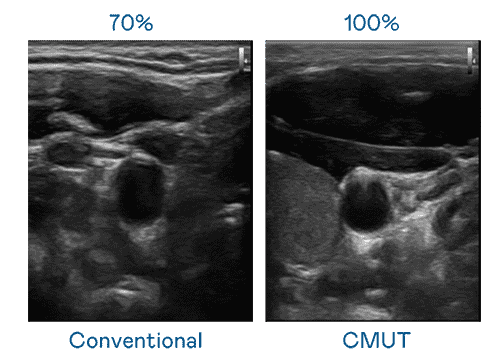

CMUT 技术是一种用电容式微机电元件来产生超音波讯号的技术。。。与传统 PZT 压电式技术相比,,,CMUT 频宽增加 30%,,更宽频的超音波讯号让影像解析度大幅提升,,,是实现高影像品质医疗超音波扫描、、、促进精准医疗发展的关键技术。。。

大频宽带来超清晰影像

超音波影像的解析度高低,,,,首先取决于探头能发出的讯号频宽。。。。蓝狮在线 CMUT 可提供高清晰的超音波讯号,,,,提供高频宽、、、、高灵敏度、、影像纹理细节更高的超音波影像,,,协助医护人员缩短影像判读时间及利用精准的医疗影像进行诊断。。